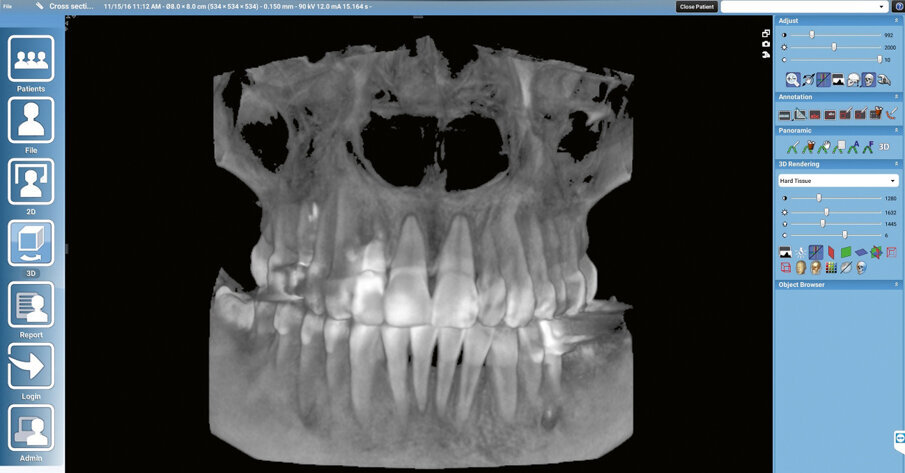

The process begins by obtaining a high-quality portrait photograph, a DVT and an STL file (Figs 1 to 3). In the case presented here, tooth 12 can no longer be preserved and needs to be replaced with an implant prosthetic restoration. Designing the prosthetic restoration forms the first stage of the implant planning sequence. In the present case, the shape of the existing tooth should be maintained. If an analogue workflow is followed, the premise for the implant is the extraction of the tooth. This scenario also forms the first step in the digital procedure described here - however, the tooth is “only” extracted virtually. We can extract the tooth digitally to design e.g. the future alveolar cavity (emergence profile) and generate an optimized emergence profile. An alveolar model is required for:

Fig. 2. DVT data set in the software program

The implant crown is designed (virtual wax-up). In the present case, the tooth being replaced serves as the template. The crown reflects the position and proportions of the original tooth. A copy of the scan file is again used as working file on which the virtual tooth extraction is performed. This allows us to go back to the original data and compare it with the working file. We define the ideal implant placement position and design the peri-implant soft tissue contours on the screen to provide an adequate emergence profile (Fig. 4). We then prepare a drill template for safe transfer of the implant position to the oral cavity. Even though most dentists are familiar with this procedure, we will briefly address the fundamentals: Basically, three data sets are required for preparing a drill template:

At the next step, we simulate the surgical procedure on the screen. The implant is inserted digitally and then a template of the procedure is exported. The conditions of the alveolar bone can be assessed to determine the bone’s fitness for the planned procedure. If necessary, the alveolar bone may be adjusted, for instance by planning a bone transplant. Alternatively, a compromise may be made and it may be preferable to opt for a cemented restoration or a change in the design instead. We take all the major decisions at the virtual implant insertion stage. The details can then be transferred to the clinical situation by means of the drill template. The position of the implant is established with the help of the wax-up (3 to 4 mm deeper). The implant angle and position should be selected so that the available bone structure can be used to optimum effect, without deviating too much from the specifications of the prosthetic restoration. In this case, the aim is to provide a screw-retained restoration. We are still using our “digital clone” to plan these steps. Once the preparatory steps have been completed, the drill template is printed (Fig. 5). In addition, the STL file of the implant model including the optimized alveolar cavity design and digital scan body (Fig. 6) are prepared to design the temporary restoration.